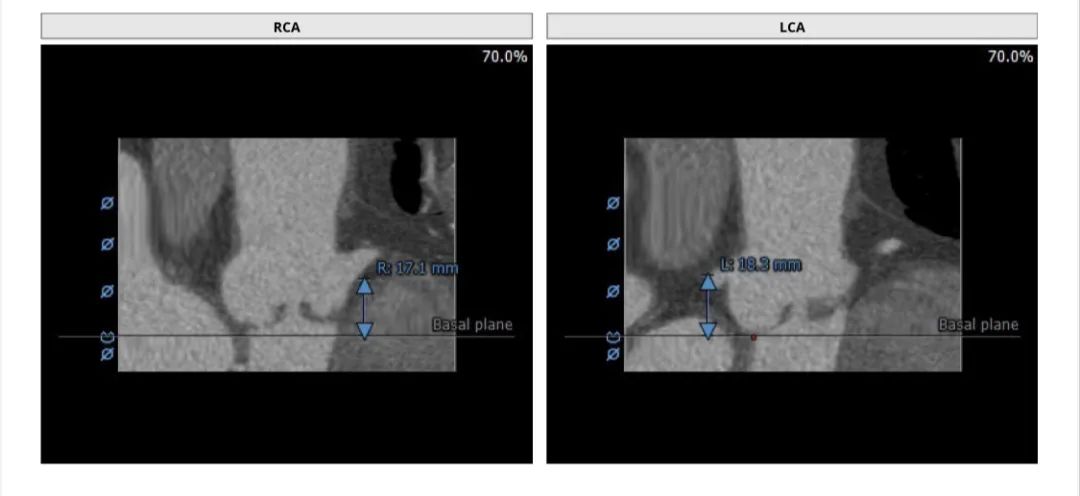

CT评估报告

左冠高度:18.3 mm,右冠高度:17.1 mm。